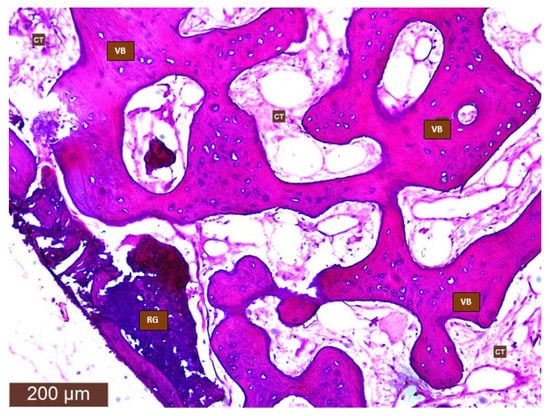

3.2. Histological Results

3.2.1. Vital Bone Formation

3.2.2. Connective Tissue

3.2.3. Residual Bone Graft Particles/Immature Bone